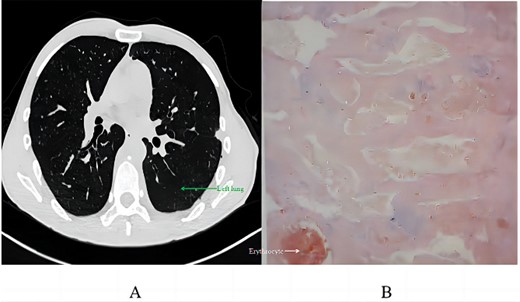

Postoperative recovery involved 420 ml of milky pleural drainage in the first day, suggestive of chylothorax. The patient followed a fat-free diet, leading to the resolution of chylous drainage by Day 12, at which point he returned to a normal diet. A chest CT on Day 14 demonstrated successful lung re-expansion without pleural effusion, permitting the removal of the chest tube. He was discharged the day after. Pathological analysis revealed vascular-like structures with red blood cells, minimal lymphocytes, consistent with a vascular tumour, diagnosed as an angioma (Fig. 4B) after immunohistochemistry tests for SOX-10 and AE1/AE3 were negative.

Postoperative analysis: (A) chest CT scan 2 months post-discharge; (B) pathological section.

Two months after discharge, a follow-up CT scan revealed no significant pneumothorax, pleural effusion, or pneumonia, with no abnormal soft tissue in the surgical area. The patient noted a significant decrease in pain since discharge.

Chylothorax, a notable complication, developed post-surgically, likely because of lymphatic vessel disruption during tumour resection. This was managed with a fat-free diet until resolution, consistent with literature on chylothorax management [9]. The pathological findings of a vascular tumour, specifically an angioma, are consistent with the origin and behaviour of the tumour. The low Ki67 index indicated a low proliferative rate, typical of benign vascular lesions [10]. The absence of SOX-10 and pan-cytokeratin (AE1/AE3) further supported the non-neurogenic, non-epithelial nature of the tumour. The 2-month follow-up, showing no significant complications or recurrence, is promising. However, given the rarity of these tumours and the potential for recurrence, long-term surveillance is recommended [11, 12].